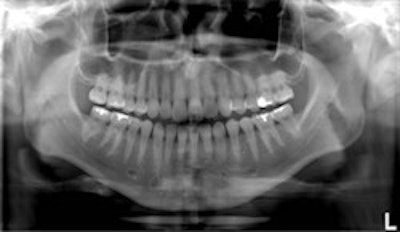

Top, standard panoramic image from a PC-1000 system using a CdTe sensor from Ajat and the PanoACT-1000 tomosynthesis software. Middle, although the anterior teeth are distorted, the posterior teeth no longer have overlapped interproximals. By manually positioning the patient in the system, the contacts are now open. Bottom, the tomosynthesis software then autocorrected the image to bring the front teeth into focus. All images courtesy of Dr. Robert Langlais. |